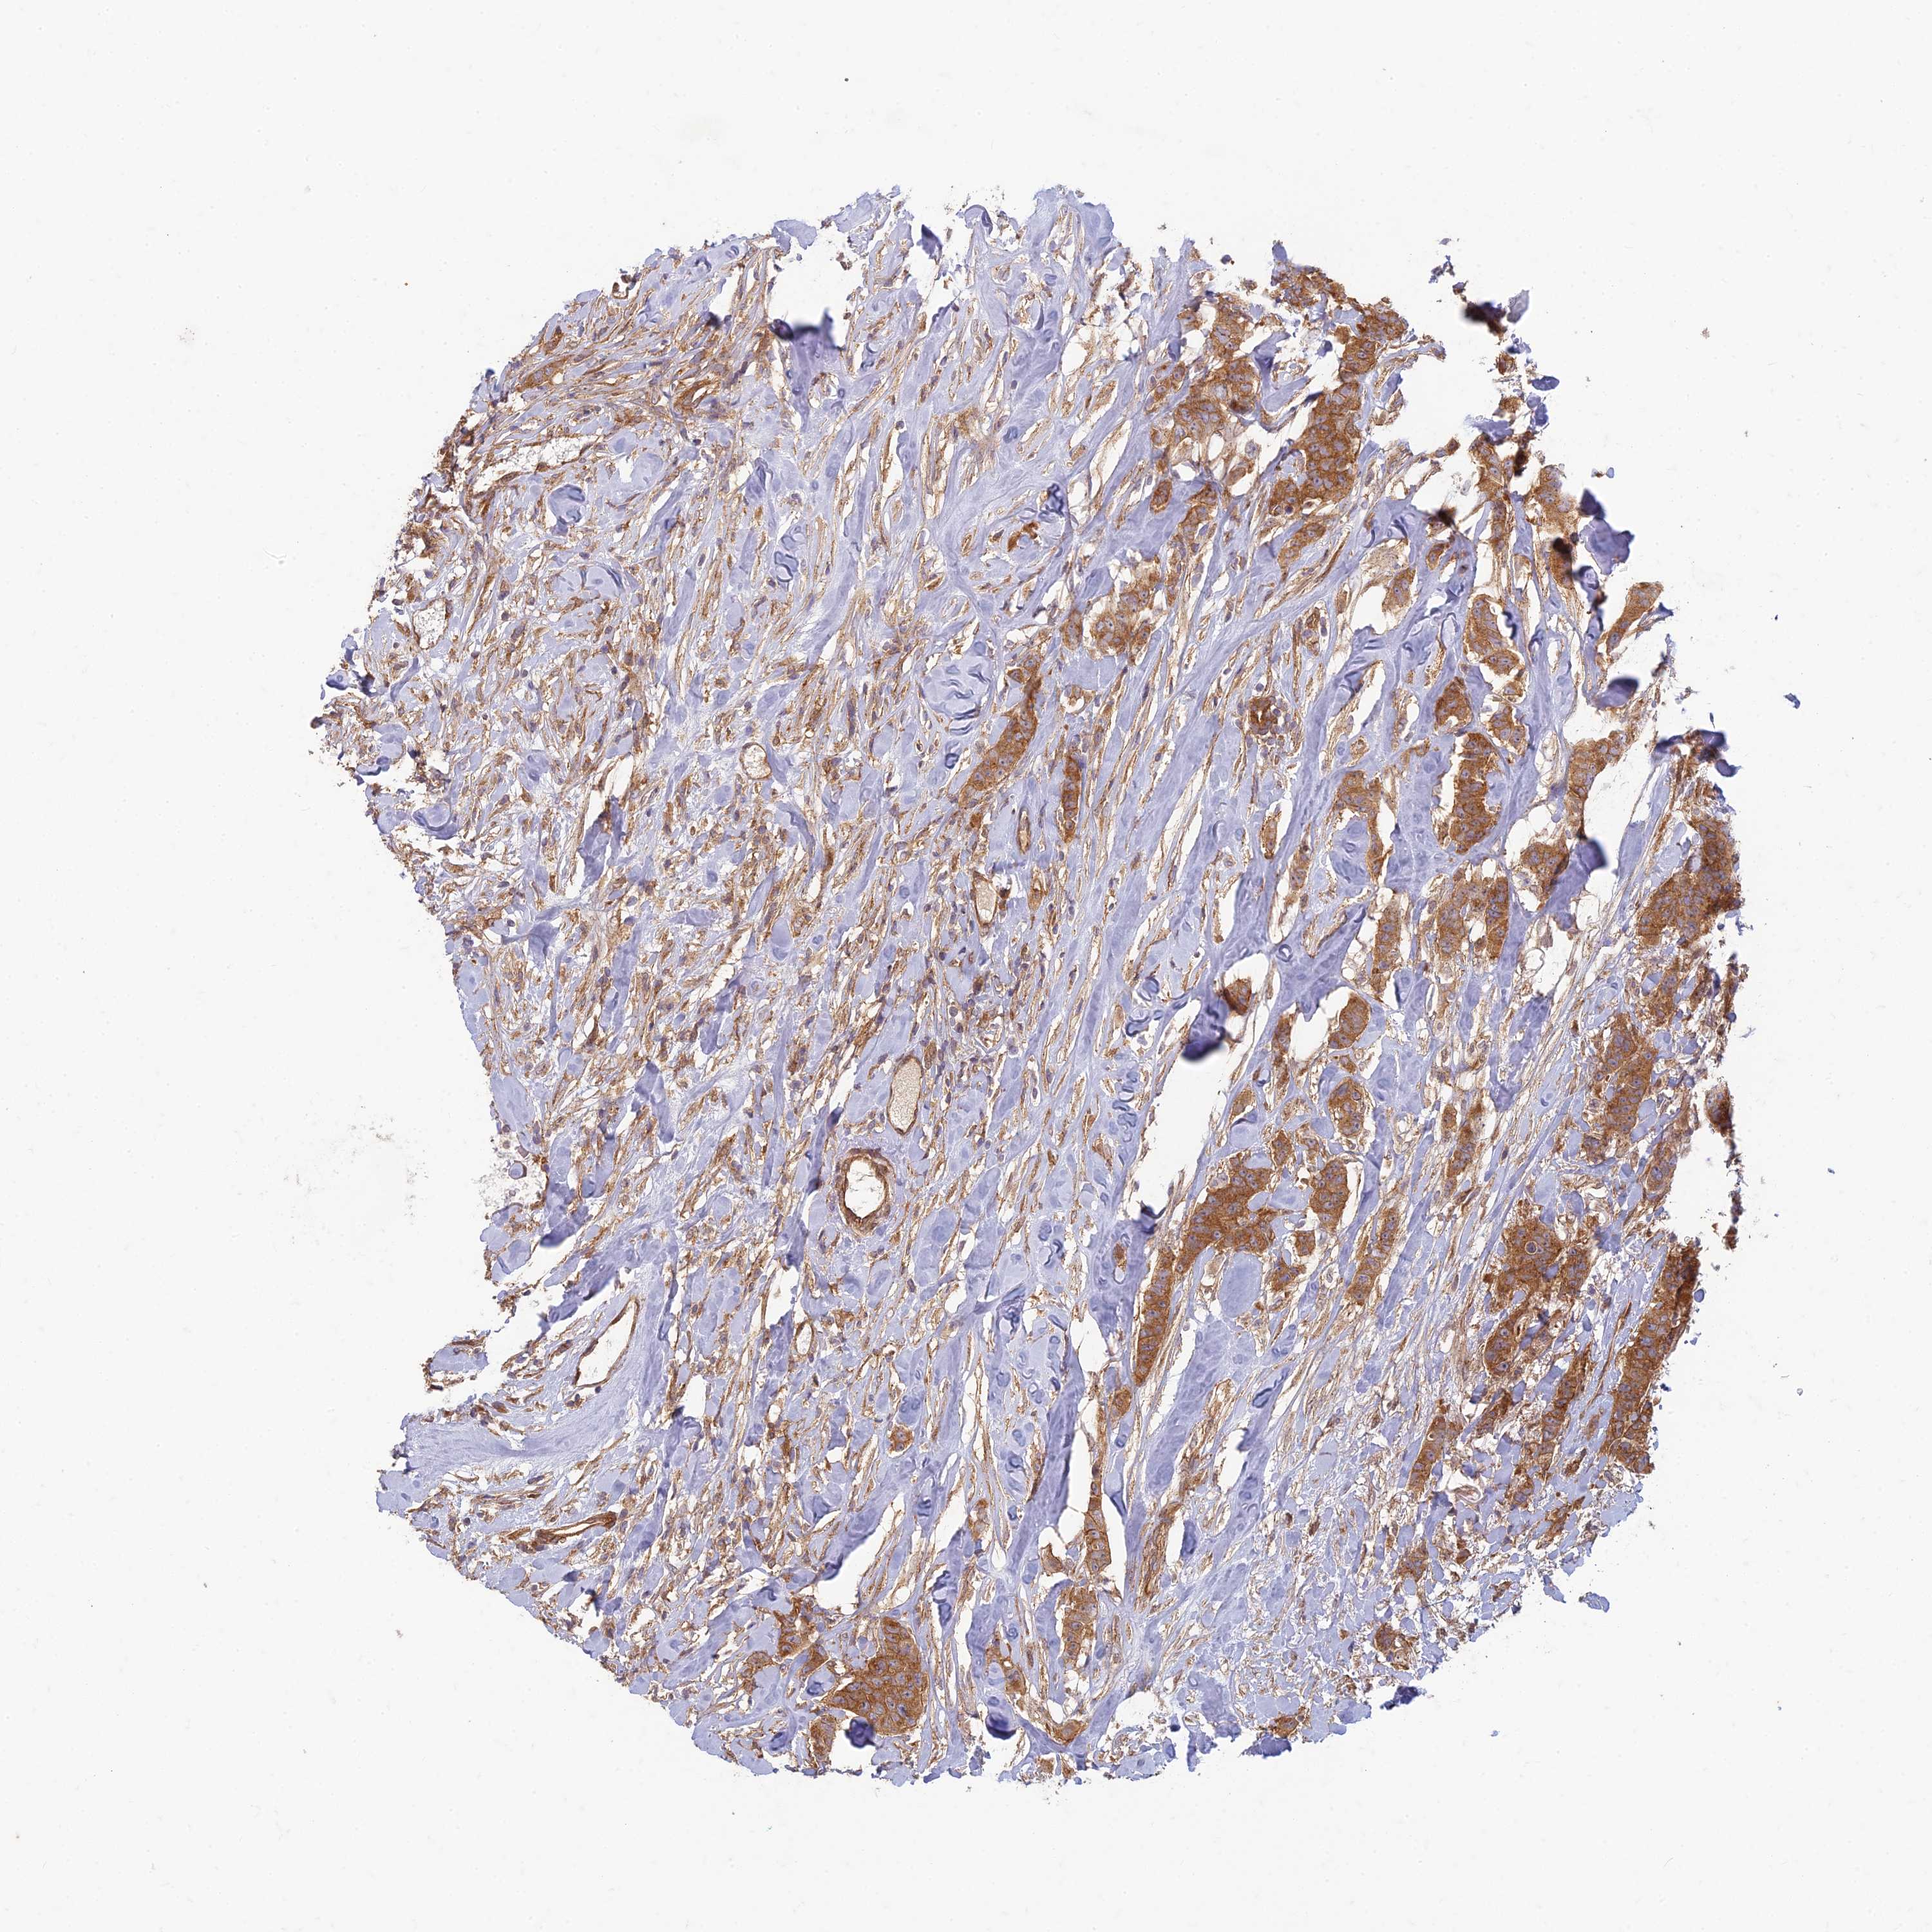

CANCER BREAST CANCER Show tissue menu

BRCA TCGA BRCA VALIDATION PROTEIN EXPRESSION